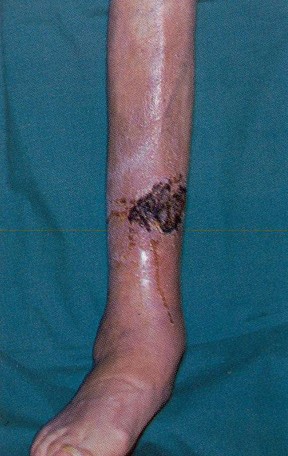

Left upper lobe abscess, right-sided pleural effusion, and left lingular segmental

pneumonia (left image). Edema, erythema, and venous ulceration in the left lower extremity

(right image). Patients with FS are prone to develope venous stasis ulcerations2.